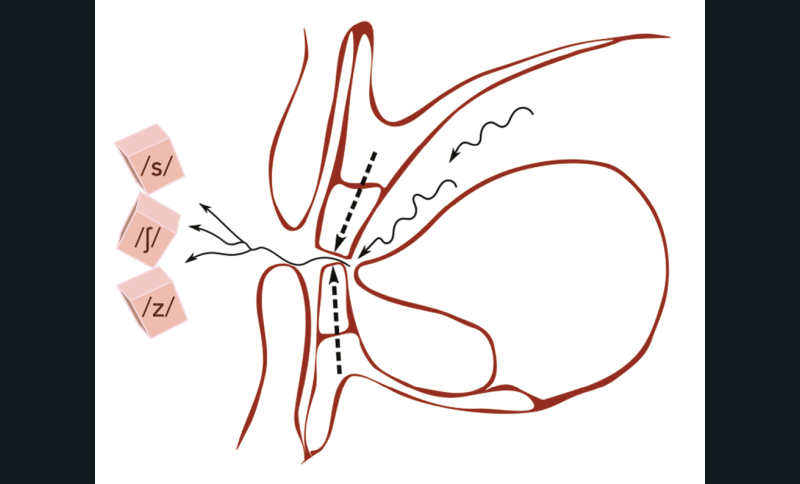

Phonation

La phonation peut également être utilisée dans la détermination de la DVO. On parle alors de dimension verticale phonétique. Le phonème où l’ELI est le minimal est le /s/. C’est pourquoi on demande au patient de prononcer lentement et sans élever la voix des mots contenant celui-ci : compter de 1 à 20 (écouter particulièrement les 5, 6, 12, 15, 16) ou de 65 à 77.

On fera ainsi, selon la psychologie du patient, prononcer des mots en concordance avec sa personnalité : « caresse », « tendresse », « paresse », « tristesse », « saucisson »… [25,26]. Il s’agit là des tests de Silverman, et un chuintement ou zozotement important lors de la prononciation est un indicateur de mésestimation de la DV (fig. 23).

Le bourrelet doit être réglé de manière à ce que le bord libre des incisives maxillaires se situe 1 mm en avant du bord libre des incisives mandibulaires. Une simple discussion avec le patient peut ensuite conforter le choix de la DVO [27] (fig. 24).